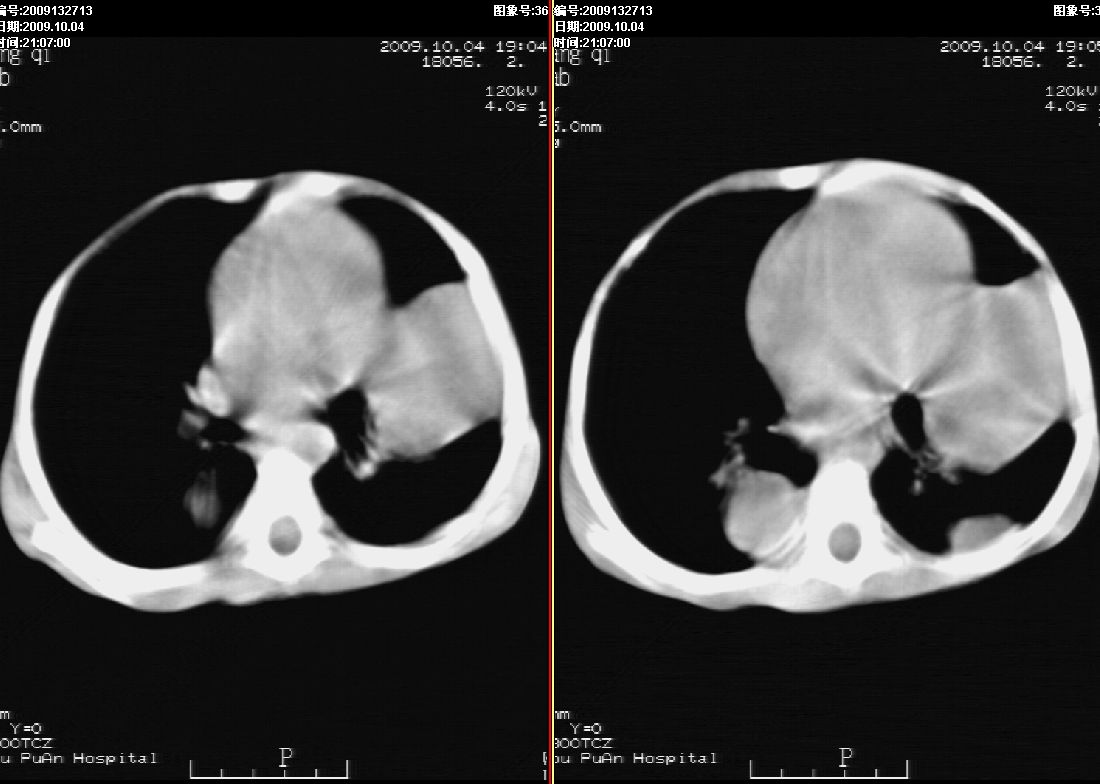

右肾巨大囊性占位病变,其内密度不均,正常肾结构消失,肝脏,肾上腺及肠管等受压移位。双肺内多发大小不等的结节及块状影。考虑右肾母细胞瘤伴双肺多发转移。

肾母细胞瘤(wilms),系儿童最常见的恶性肿瘤,好发于3岁以下儿童,瘤体较大,主要由胚胎性肉瘤样细胞和上皮样细胞构成,临床以腹部肿块;血尿和高血压为主要体征。

ct表现:密度不均匀的大肿块存在;出血和坏死。与神母鉴别点:wilms易向颅脑转移,而神母易往肺转移。

ct表现:密度不均匀的大肿块存在;出血和坏死。与神母鉴别点:wilms易向肺转移。而神母易往颅脑转移.